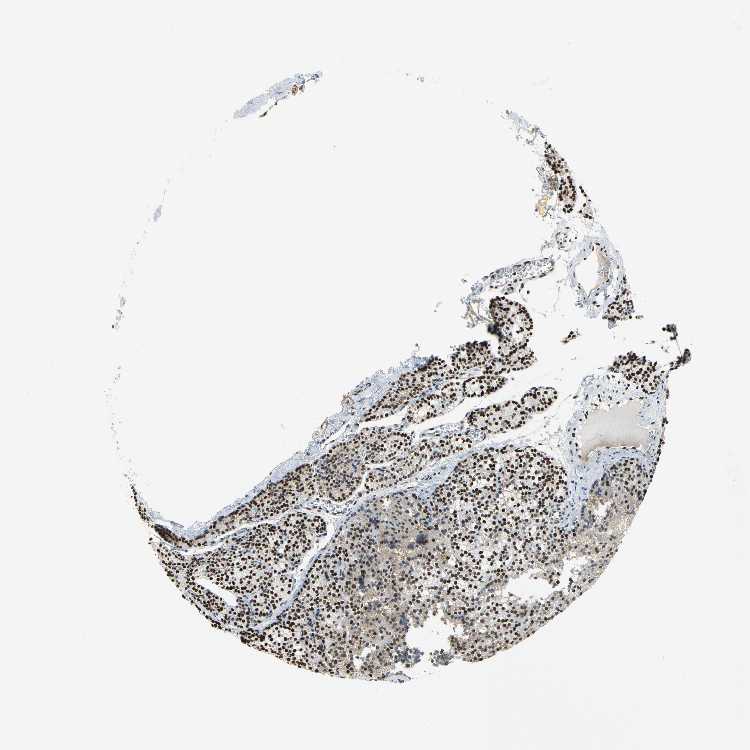

TISSUE PRIMARY DATA PARATHYROID GLAND Show tissue menu

PARATHYROID GLAND - Antibody stainingi

Antibody staining in the annotated cell types in the current human tissue is reported as not detected, low, medium, or high, based on conventional immunohistochemistry profiling in selected tissues. This score is based on the combination of the staining intensity and fraction of stained cells.

Each image is clickable and will lead to virtual microscopy that enables deeper exploration of all samples and also displays staining intensity scores, fraction scores and subcellular localization as well as patient and tissue information for each sample.

Antibody HPA003506Antibody CAB005873

Glandular cells MediumHigh